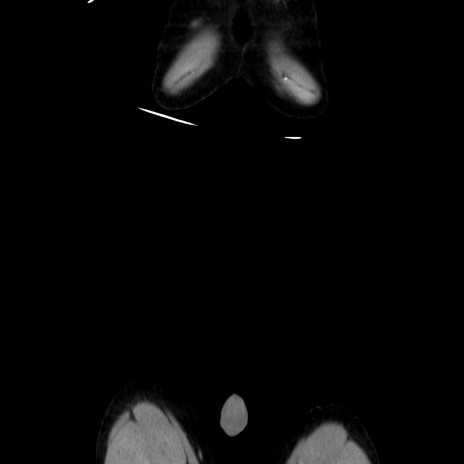

症例37(冠状断像)

【症例】40歳代 男性

【主訴】腹痛

【現病歴】4時間ほど前に電車に乗車中に臍部上より腹痛出現。徐々に増悪し起立困難となり、救急外来受診。生ものは数日食べていない。今朝お雑煮を食べた。

【身体所見】BT 36.8℃、BP 117/84mmHg、HR 91/min、SpO2 97%、苦悶様、腹部:臍上部広範囲圧痛あり、反跳痛±

【データ】WBC 8100、CRP 0.03